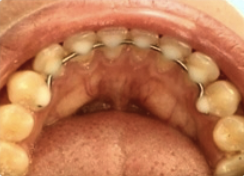

La ferulización lingual consiste en colocar un alambre por la parte lingual de los

dientes anteriores (para que no se vea y

sea una retención estética). El alambre va unido a cada diente con composite. La ferulización es permanente.